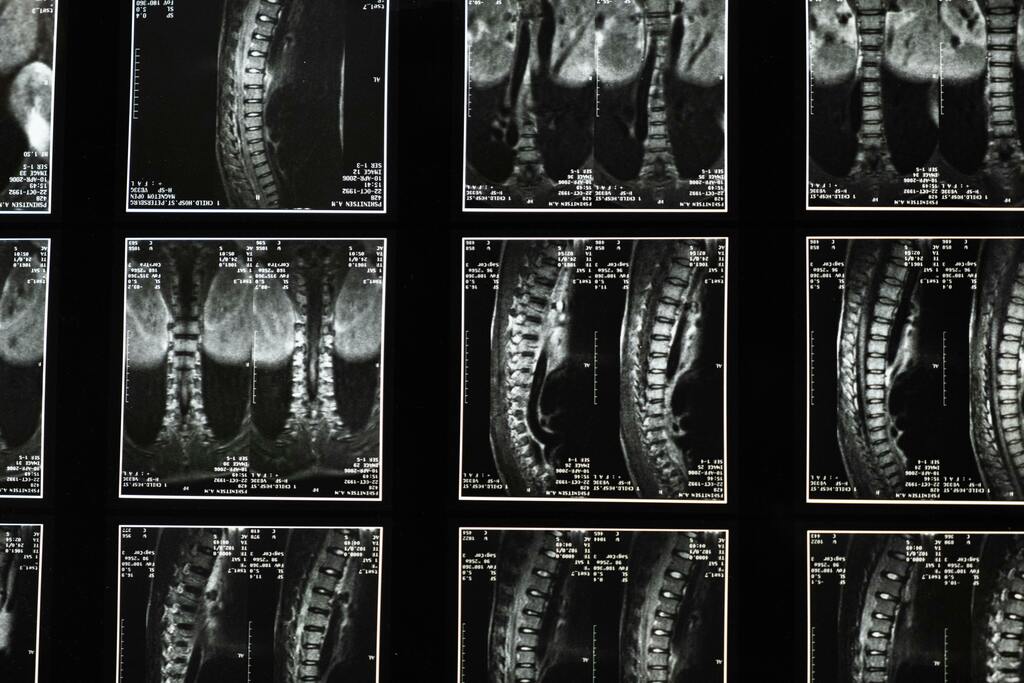

We start by listening. You’ll meet with Dr. Vincenzo De Luca to discuss your symptoms, health history, and goals. A full spinal exam helps us understand what your body needs.

Utilizing safe and effective hands-on techniques, we focus on making precise adjustments to realign your spine. This careful realignment not only improves your spinal health but also enhances the overall function of your nervous system—supporting your body's natural ability to heal and thrive. Our approach is designed to promote well-being in a safe and nurturing environment, allowing you to experience the benefits of a balanced spine and optimal nervous system function.